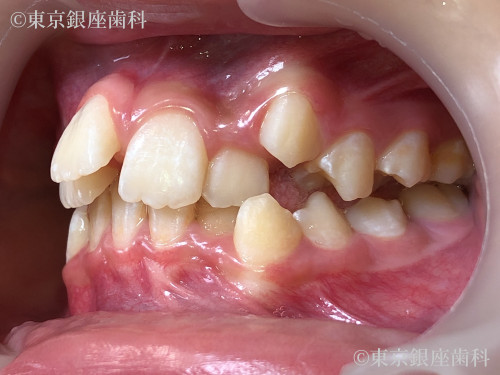

After

10代 女性

治療期間 11ヶ月 費用 65万円(税込)

インビザライン:ファースト